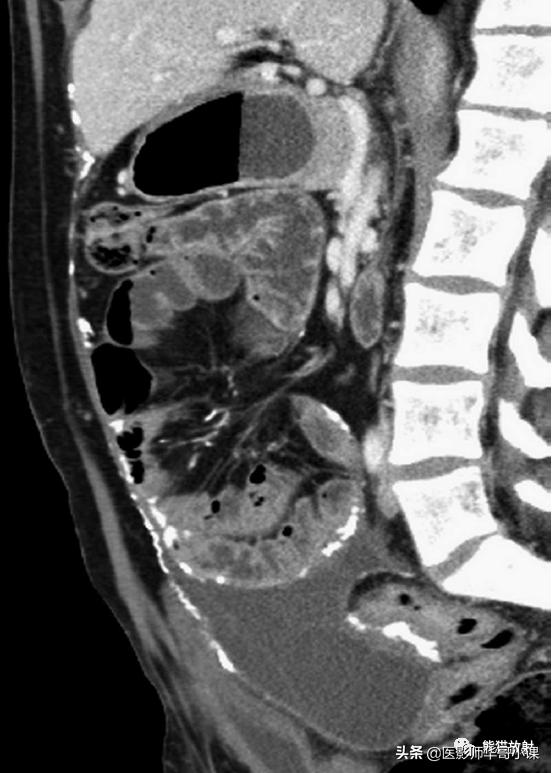

包虫病主要是感染细粒棘球绦虫所致。腹膜包虫病常常由于肝包虫病外伤或手术破裂而发生。 腹膜出现囊状占位性病变,囊壁薄,常有分隔 。腹膜种植时CT是首选检查方法(图)。边缘环形钙化具有提示诊断意义。

腹膜包虫病。增强CT显示一个大而多分隔的囊性腹膜肿块。囊内见子囊,多发分隔的蜂窝状表现,边缘钙化为其特征性表现。